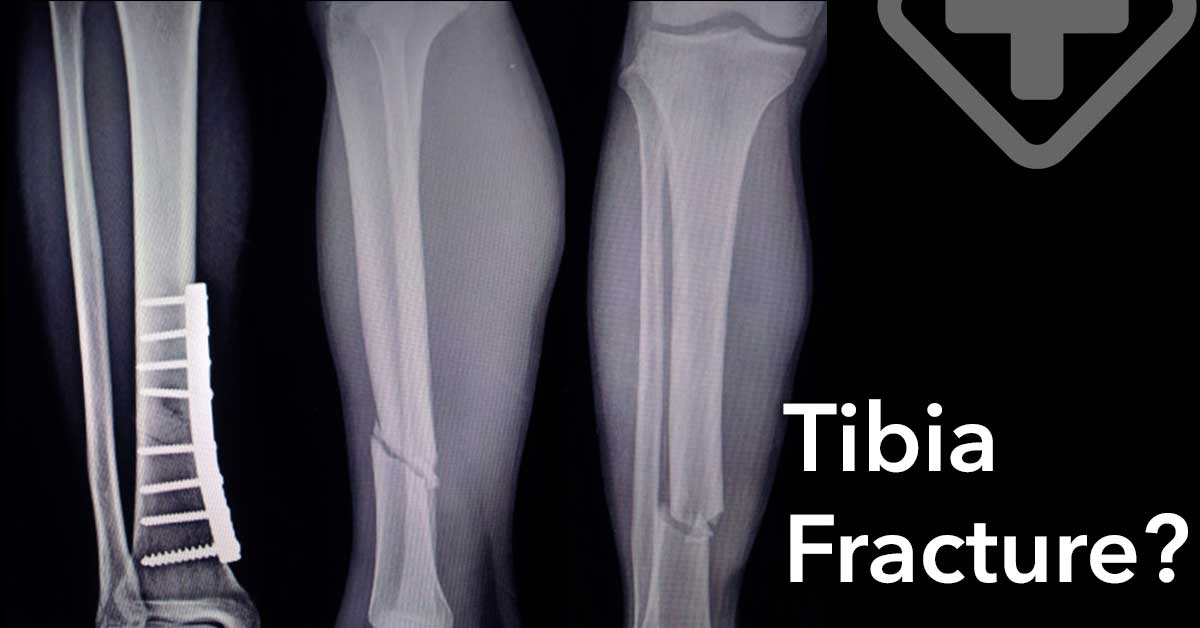

In severe cases, surgery may be necessary to ensure that the bone heals properly. The Orthopedist Surgeon or Traumatologist can use metal plates and screws to fix the bone in place, allowing optimal bone recovery with minimal long-term damage. This procedure is known as osteosynthesis.

The Orthopedist Surgeon or Traumatologist may also use metal rods or pins to drive them through the bones, above and below the fracture. These will be attached to a rigid frame called an external fixator and will hold the bone in place. The specialist who treats tibia fractures is the Orthopedist or Traumatologist.